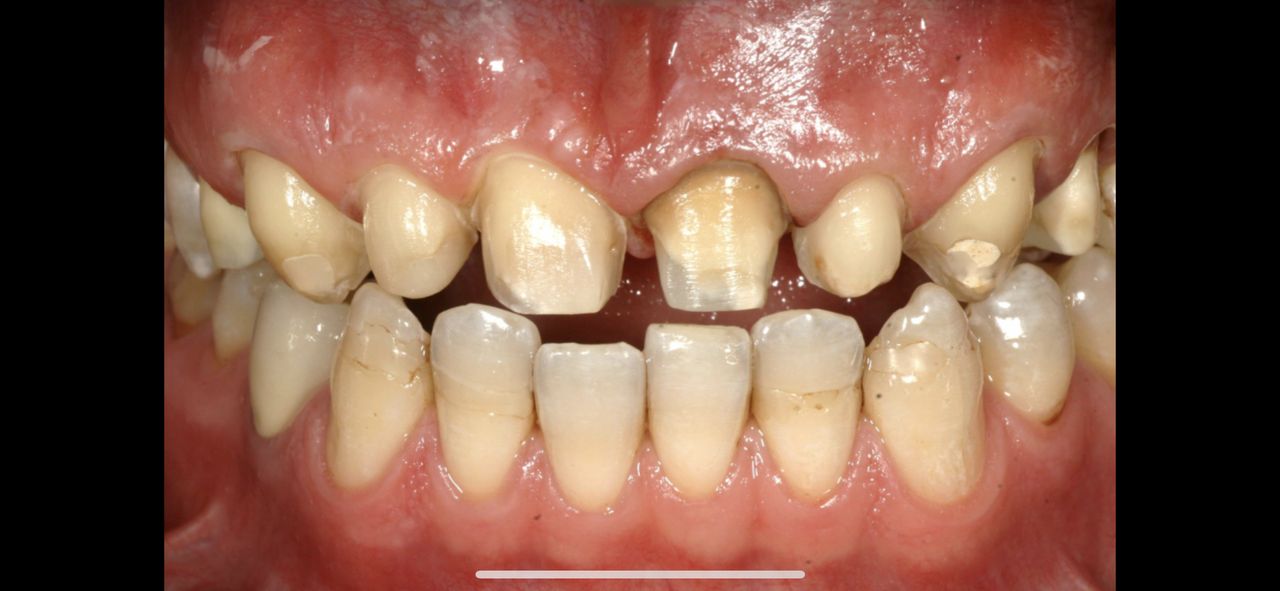

Pan dok.Polakowski to profesjonalista, tam gdzie nikt nie chciał zająć się moimi zębami

P.dok wyczarowal piękny uśmiech.

Dziękuję, i z czystym sumieniem mogę polecić każdemu kto ma problemy z zębami.

• Duo-Dent odbudowa zębów  •